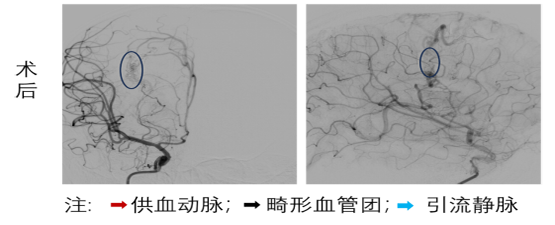

面对生命垂危的患儿,姚声涛教授团队组织全科讨论,制定详细的治疗方案,采用介入动静脉畸形栓塞术。手术无需开颅,仅通过患儿大腿根部的股动脉做一个微小穿刺口,在 DSA 的引导下,将一根纤细的微导管精准 “导航” 至大脑深处的畸形血管团内。随后,向畸形血管团内注入特殊的 “生物胶” 栓塞剂,让药剂在血管内部层层填满、牢牢 “堵死” 这个异常的血管 “短路”,从根源上消除再次出血的隐患。凭借团队娴熟的操作技巧和精准的治疗决策,两台手术均顺利完成,整个手术过程精准微创,最大程度减少了对患儿脑组织的损伤,为术后快速恢复打下了基础。

首先接受治疗的患儿术后恢复超出预期,很快就脱离了生命危险,意识清晰、肢体活动正常,经过一段时间的康复观察,已完全康复出院,重新回到了课堂和小伙伴身边。另一名患儿也已度过危险期,各项生命体征平稳,能独立行走生活。